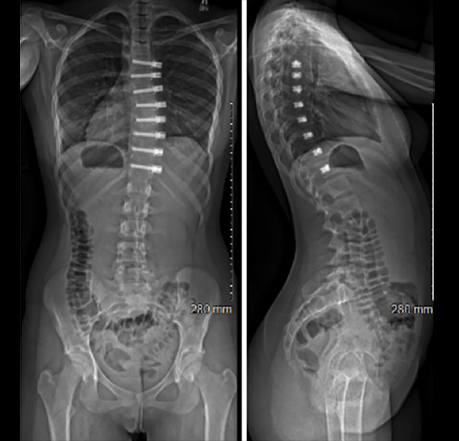

A) Tethering